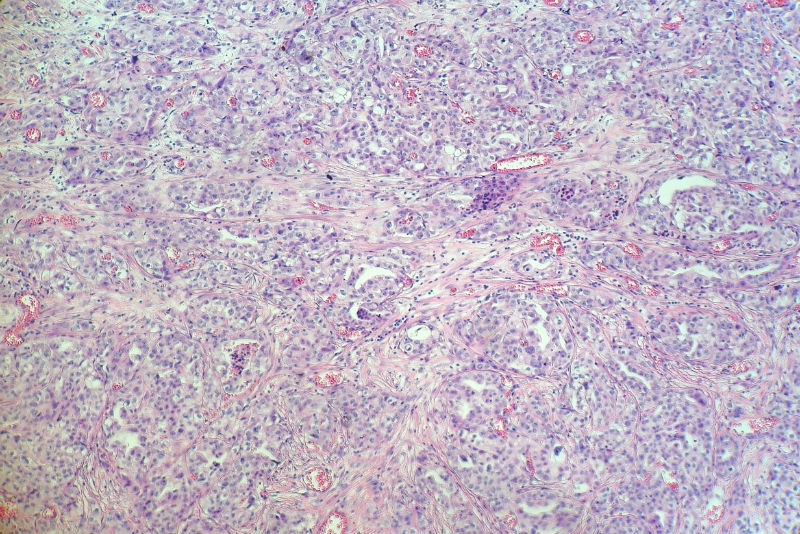

男,82岁,小肠穿孔紧急手术。

大体,小肠一段,长约60厘米,与粘膜面可见三个溃疡型肿物,肠系膜淋巴结肿大。

肿瘤呈巢片状分布,细胞大小相对一致,胞浆丰富,胞核呈细颗粒状,可见小核仁,血管较丰富,考虑神经内分泌肿瘤,加做免疫组化(Ki67、Syn、NSE、CgA、CD56)分级。

腺癌,部分为神经内分泌癌